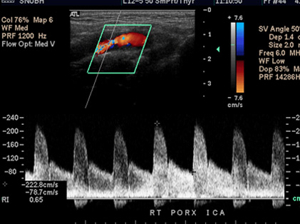

- 도플러 초음파 검사 (Duplex ultrasound)

- 하지정맥류 진단에 가장 중요하고 기본이 되는 비침습 검사입니다.

- 혈관 초음파로 혈관 구조를 확인하고 도플러를 통해 혈액의 흐름 방향, 속도, 역류 여부 및 역류 시간을 측정합니다.

- 이 검사를 통해 정맥 내 판막 손상 부위에서 혈액이 역류하는 정도를 평가하고, 정맥류의 원인이 되는 혈관을 정확히 찾아낼 수 있습니다.

- 도플러 초음파 검사 (혈관초음파)

- 가장 기본이며 핵심적인 검사입니다.

- 혈관 내 혈류의 방향, 속도, 역류 여부와 역류 시간을 직접 측정할 수 있습니다.

- 정맥 판막의 손상 부위를 확인하고, 혈액이 역류하는 정도를 정량적으로 평가합니다.

- 정맥류의 원인이 되는 혈관을 정확히 찾아내고, 혈관 구조와 기능을 동시에 볼 수 있어 진단과 치료 계획 수립에 가장 효과적입니다.

- 도플러 초음파 검사 (Doppler Ultrasound)

- 일반 초음파의 원리에 도플러 효과를 적용한 검사로, 움직이는 혈액의 속도와 방향을 실시간으로 측정할 수 있습니다.

- 혈관 내 혈류의 특성을 분석해 혈류가 정상적으로 흐르는지, 역류나 협착이 있는지 평가할 수 있습니다.

- 혈관의 기능적 상태를 파악하는 데 중요한 역할을 하며, 하지정맥류, 동맥 협착, 혈전 등 혈관 질환 진단에 쓰입니다.